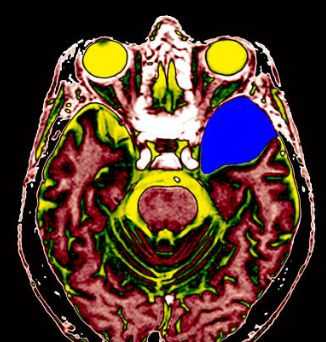

МРТ головного мозга. Т2-взвешенная аксиальная томограмма. Арахноидальная киста. Цветовая обработка изображения.

Арахноидальные кисты представляют собой скопление ликвора между листками расщепленной паутинной оболочки. Арахноидальная киста обычно не сопровождается другими мальформациями. Незначительная часть арахноидальных кист имеет приобретенное происхождение - следствие лептоменингита, операции или кровоизлияния. Частота составляет около 1% от внутричерепных образований. Соотношение полов М:Ж, как 4:1. Типичная локализация - средняя черепная ямка (в области Сильвиевой борозды 50%), межполушарная щель, мосто-мозжечковый угол (11%), за скатом или на уровне четверохолмия (10%), в области червя мозжечка (9%), реже в области межножковой и предмостовой цистерн (3%), а также супраселлярной и хиазмальной цистерн. Ретроцеребеллярная арахноидальная киста довольно часто встречаются за мозжечком и отличима от mega cisterna только по неизменённой задней черепной ямке. Содержимое кисты чисто ликворное, стенки гладкие, чётко очерченные, внутри кисты могут быть перегородки. Мелкие арахноидальные кисты очень трудно увидеть. Меняя ширину окна и его уровень на Т1-взвешенных МРТ изображениях можно заметить, что киста чуть светлее ликвора. Дифференциальная диагностика с эпидермальными кистами лучше осуществляется с помощью МРТ последовательности FLAIR. Эпидермальные кисты становятся яркими, в отличие от гипоинтенсивных арахноидальных.

Кисты головного мозга - это аномалии его развития. При МРТ в СПб мы видим задачу в дифференциальной диагностике с кистозными формами опухолей. При МРТ головного мозга некоторые виды кист, особенно дермоидные, сами напоминают опухоль.

Арахноидальные кисты представляют собой скопление ликвора между листками расщепленной паутинной оболочки. Арахноидальная киста обычно не сопровождается другими мальформациями. Незначительная часть арахноидальных кист имеет приобретенное происхождение - следствие лептоменингита, операции или кровоизлияния. Частота составляет около 1% от внутричерепных образований. Соотношение полов М:Ж, как 4:1. Типичная локализация - средняя черепная ямка (в области Сильвиевой борозды 50%), межполушарная щель, мосто-мозжечковый угол (11%), за скатом или на уровне четверохолмия (10%), в области червя мозжечка (9%), реже в области межножковой и предмостовой цистерн (3%), а также супраселлярной и хиазмальной цистерн. В зависимости от размера предложено делить кисты на 3 типа (Galassi, 2006), что однако, не имеет практического значения. Ретроцеребеллярная арахноидальная киста довольно часто встречаются за мозжечком и отличима от mega cisterna только по неизменённой задней черепной ямке. При МРТ головного мозга содержимое кисты чисто ликворное, стенки гладкие, чётко очерченные, внутри кисты могут быть перегородки. Мелкие арахноидальные кисты очень трудно увидеть при МРТ головного мозга. Меняя ширину окна и его уровень на Т1-зависимых МРТ изображениях можно заметить, что киста чуть светлее ликвора. Дифференциальная диагностика с эпидермальными кистами лучше осуществляется с помощью МРТ последовательности FLAIR. На них при МРТ головного мозга эпидермальные кисты становятся яркими, в отличие от гипоинтенсивных арахноидальных. Вероятно, вариантом арахноидальной кисты является нейроэпителиальная киста, которая при МРТ головного мозга имеет типичное расположение в области хориоидальной щели.